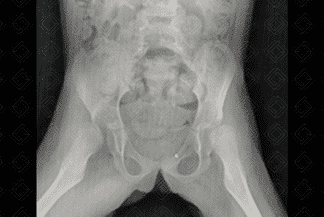

Texto alternativo para a imagem Figuras 4 e 5. Créditos: Dra. Elazir Mota - Rio de Janeiro/RJ

Descrição das imagens: Radiografia de quadril AP e Lowenstein (posição da rã). Paciente infantil neuropata. Observa-se luxação superior e lateral dos quadris bilateralmente. A medida mais usada nas radiografias é a linha de Shenton.

2. Radiografia de quadril: E xame realizado nos lactentes mais velhos, após 4-6 meses, momento no qual a epífise femoral inicia sua ossificação (neste contexto não há mais janela acústica para realização do ultrassom de quadril). Algumas linhas devem ser analisadas:

• Linha de Hilgenreiner : Uma linha horizontal traçada através do topo das áreas claras da cartilagem trirradiada;

• Linha de Perkins: É uma linha vertical perpendicular à linha de Hilgenreiner que tangencia a margem acetabular lateral. Estas duas linhas dividem o quadril em quatro quadrantes, devendo a cabeça femoral estar situada nos quadrantes inferior e medial;